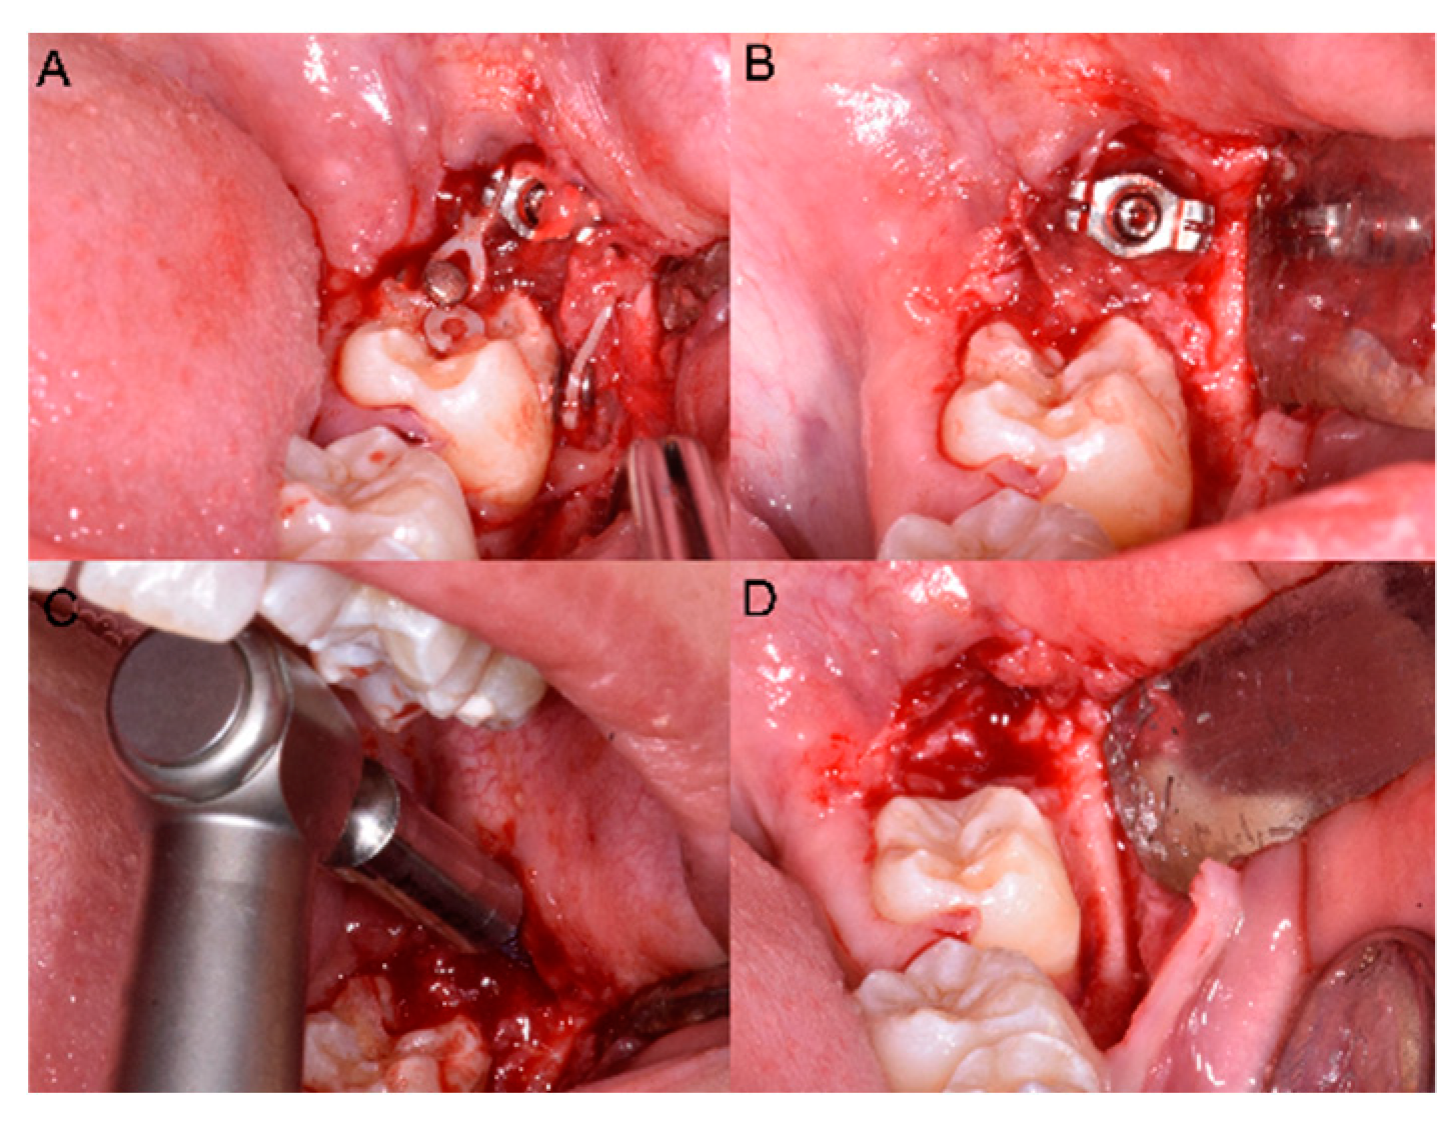

At the end of therapy the miniscrew was removed (Figure 4) and the other impacted MM2 was treated both with the same miniscrew and with the same orthodontic surgical procedure.

Figure 4.

(A,B) The elastic chain, brackets and (C) the miniscrew removal. (D) The final position in the arch of 3.7.